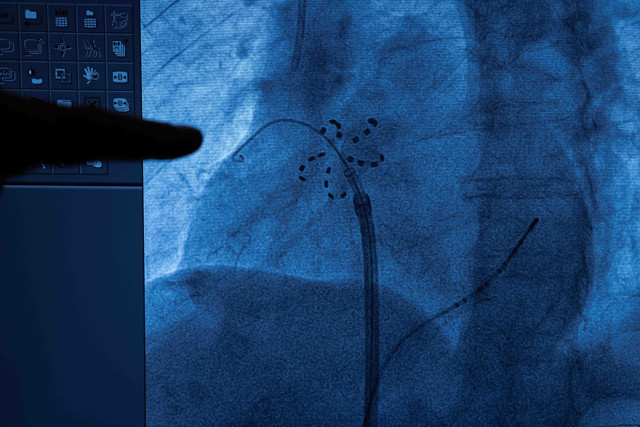

Yeni nesil tedavi yöntemi hakkında önemli bilgiler paylaşan Prof. Dr. Kılıçaslan, “Daha önce radyo frekans ve kriyoablasyon yöntemleri kullanıyorduk. Radyo frekans ve kriyoablasyon ile yapılan ablasyonlarda kalbin çevresindeki dokular da etkilenebiliyor ve nadir de olsa akciğer damarlarında daralma, yemek borusunun ve solunum sinirinin hasarlanması gibi ciddi komplikasyonlar görülebiliyordu. PFA ile bu önemli risklerin hiçbiri görülmüyor. PFA yöntemi, kasıktan damar yoluyla ilerletilen kateterle uygulanıyor. Kateter ucundaki elektrot, problemli dokulara yüksek frekanslı elektrik dalgası gönderiyor ve bu dokuların elektriksel aktivasyonu ortadan kalkıyor. Böylece ritim bozukluğu tedavi edilmiş oluyor” dedi.